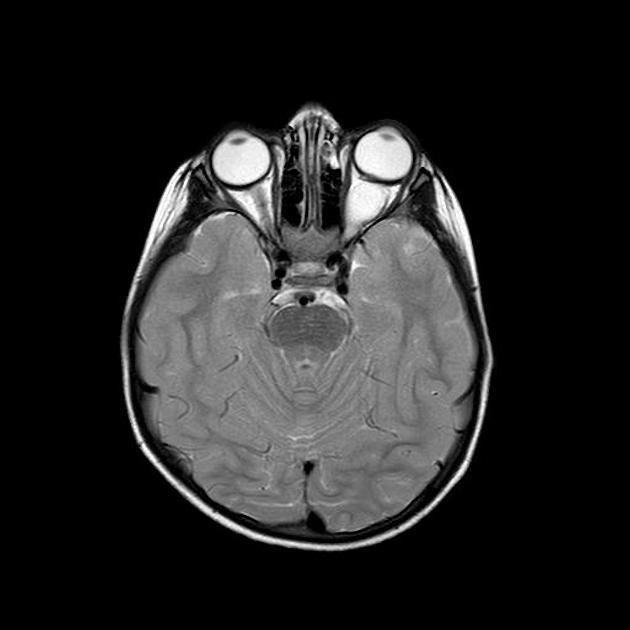

图 5 MRI 检查轴位 T2WI,冠状位 T2WI 和矢状位 T1WI 序列显示左侧视神经脊椎内段可见类圆形肿物,呈稍长 T1 长 T2 异常信号

图 6 MRI 检查轴位 T2WI,T1WI 和矢状位 T1WI 增强序列显示,左侧视神经肌锥内段见类圆形稍长 T1 长 T2 明显异常信号,呈明显强化